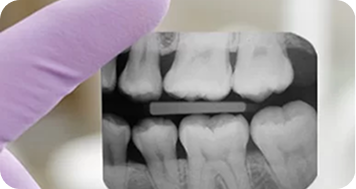

Tomografia Cone Beam e lesões periapicais

A tomografia Cone Beam é mais precisa que a radiografia odontológica na detecção de lesões periapicais. Entenda mais neste conteúdo